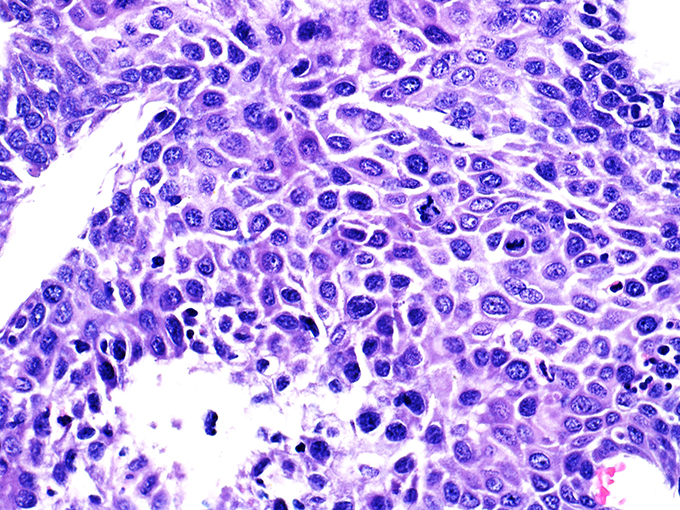

Area 1 - Soft Bx CIN 2 40x - High Power |

![]() Case 1